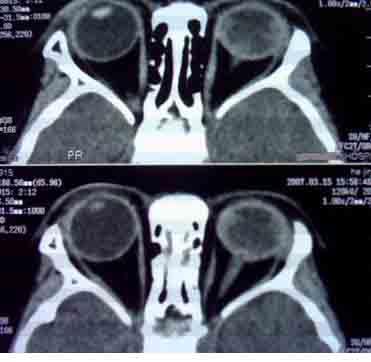

患者,偶然发现左眼无光感,平时,无明显不适,眼外观无明显异常。

首先考虑视网膜母细胞瘤。

支持视网膜母细胞瘤诊断.

支持左侧视网膜母细胞瘤,可惜没有钙化。

大家有没有想到有哪些需同成视网膜细胞瘤鉴别诊断的疾病?正是没有钙化,所以此病首先更应该考虑什么?请大家说说看。

ct检查:(1)眼内高密度肿块:(2)肿块内钙化斑,30~90%病例有此发现可作为诊断根据;(3)视神经增粗,视神经孔扩大,说明肿瘤向颅内蔓延。

1.ct表现:眼球内均匀高密度肿块,有增强,并多有点状或团块状钙化,在3岁以下的儿童有极大的诊断价值。可见相关视网膜下积液。